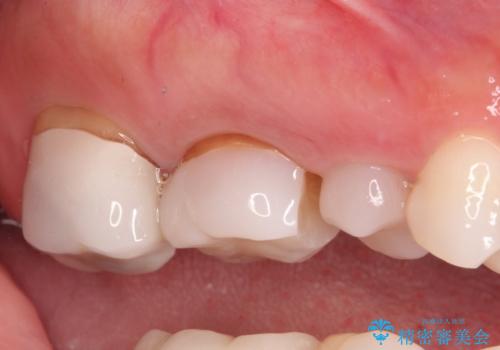

- 以前、他院で保険治療の被せ物を入れた歯が欠けてしまったことを主訴に来院されました。

その他の歯も適合が悪く治療が必要でしたので、3歯まとめて治療を行いました。

歯肉縁下マージンに対して矯正的挺出などの治療の選択肢や、根管治療の提案をしましたが、患者様との話し合いにより歯冠修復のみ行なっております。